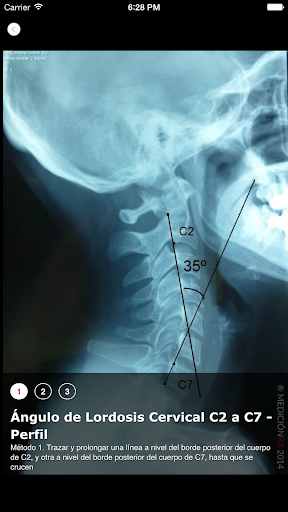

Descripción y el trazado de técnicas de medición radiológicas en ortopedia y traumatología. 120 imágenes radiográficas de alta calidad. Dirigida a kinesiólogos especialistas de las áreas de terapia manual (RPG, Osteopatía, etc), y afines. Podrá realizar su búsqueda ingresando desde "regiones", "patologías" o "mediciones". También podrá ingresar la palabra clave en la lupa de búsqueda. No es el objetivo de esta app, reemplazar a la evaluación clínica que realizamos a nuestros pacientes. Tiene como objetivo explorar los métodos de medición en los estudios radiológicos complementarios, y demostrar y cuantificar los cambios radiológicos obtenidos luego de los tratamientos kinésicos. Esta aplicación se encuentra disponible en Español, Inglés y Portugués.